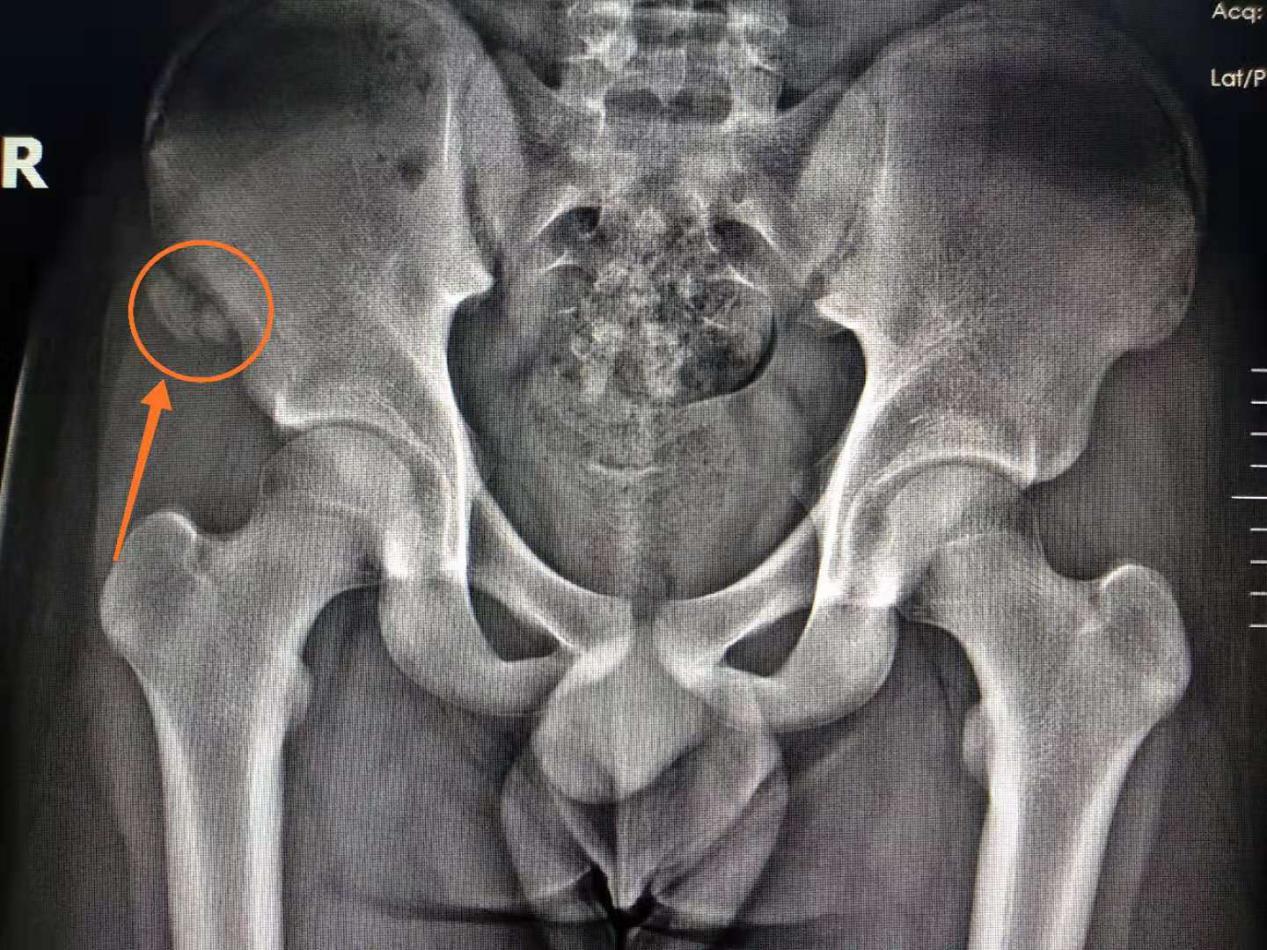

2. 14岁,男性中学生,在体育课100米短跑冲刺时突然感到左髂部疼痛不适,随即摔倒在地,当即送到我院诊治,X线片示:右髂前上棘撕脱性骨折。

影像学检查:X线示右髂前上棘撕脱性骨折,骨碎片向下前侧移位。

X线示右髂前上棘撕脱性骨折,骨碎片向下前侧移位。